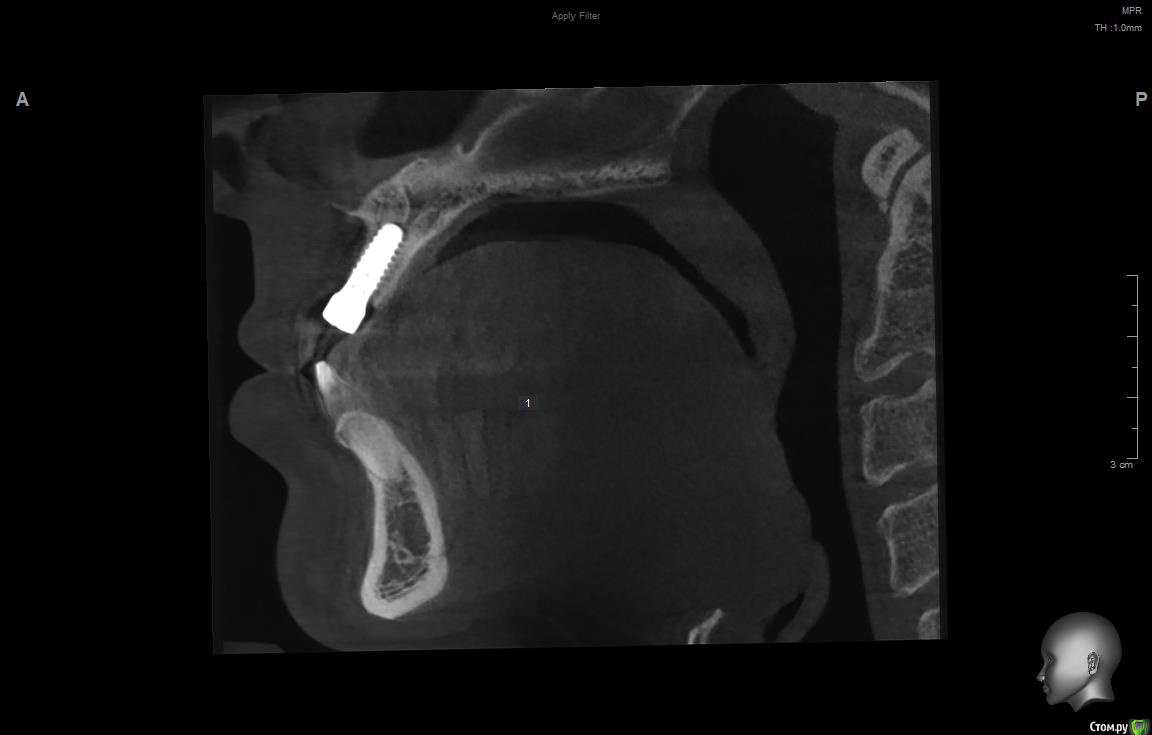

jm3300 Опубликовано 11 сентября, 2019 Поделиться Опубликовано 11 сентября, 2019 Имплант( система, производитель) не известен, формирователи подобные не видел, шестигранные отвертки не подходят( на формике отверстие под четырехгранник). Данных на имплант у пациента нет. В клинике, где ставили, якобы, не помнят что ставили. Может кто встречался с ними? Ссылка на комментарий

АнтонТЛТ Опубликовано 11 сентября, 2019 Поделиться Опубликовано 11 сентября, 2019 (изменено) Что за мода выкладывать срезы Кт, на которых всё фонит. Лучше уж прицельный снимок. Возможно это конмет, у них квадратный шлиц. Изменено 11 сентября, 2019 пользователем АнтонТЛТ 2 Ссылка на комментарий

dr Alexandr Опубликовано 14 сентября, 2019 Поделиться Опубликовано 14 сентября, 2019 Похож на Конмет, у этой системы своя протетика и ортопедический набор! Отвёртка у них 6 гр только меньше, нужно попробовать выкрутить фдм, там понятнее будет 1 Ссылка на комментарий